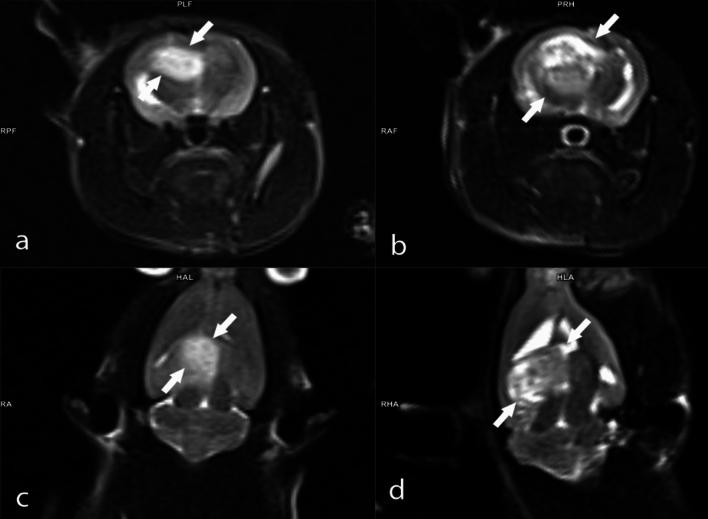

Limited advancements in managing malignant brain tumors have resulted in poor prognoses for glioblastoma (GBM) patients. Standard treatment involves surgery, radiotherapy, and chemotherapy, which lack specificity and damage healthy brain tissue. Boron-containing compounds, such as boric acid (BA), exhibit diverse biological effects, including anticancer properties. This study aimed to examine whether boron supplementation, as BA, can inhibit glioblastoma growth in a xenograft animal model. Using MRI-based tumor size measurement, survival rates, hematological, clinical biochemistry analyses, and genotoxicity parameters, we assessed the impact of BA. Histopathological, immunohistochemical, and immunofluorescence examinations were also conducted. All BA doses (3.25, 6.5, and 13 mg kg b.w.) extended survival compared to GBM controls after 14 days, with a dose-dependent anti-GBM effect observed in MRI analyses. BA treatment improved hematological (WBC and PLT counts) and biochemical parameters (LDL-C, CREA, and ALP). Histopathological examination revealed a significant reduction in tumor diameter with 6.5 and 13 mg kg BA. Immunohistochemical and immunofluorescence staining showed modulation of intracytoplasmic Ki67, cytoplasmic CMPK2, and GFAP expressions in tumor cells post-BA treatment. Additionally, BA did not increase micronuclei formations, indicating its non-genotoxic nature. In conclusion, targeting tumor suppressor networks with boron demonstrates significant therapeutic potential for GBM treatment.

恶性脑肿瘤治疗进展有限,导致胶质母细胞瘤(GBM)患者预后不良。标准治疗包括手术、放疗和化疗,这些方法缺乏特异性,会损害健康脑组织。含硼化合物,如硼酸(BA),具有多种生物学效应,包括抗癌特性。本研究旨在探讨以BA形式补充硼是否能在异种移植动物模型中抑制胶质母细胞瘤的生长。我们使用基于MRI的肿瘤大小测量、生存率、血液学、临床生化分析和遗传毒性参数来评估BA的影响。还进行了组织病理学、免疫组织化学和免疫荧光检查。与GBM对照组相比,所有BA剂量(3.25、6.5和13mg/kg体重)在14天后均延长了生存期,MRI分析显示出剂量依赖性的抗GBM效应。BA治疗改善了血液学参数(白细胞和血小板计数)和生化参数(低密度脂蛋白胆固醇、肌酐和碱性磷酸酶)。组织病理学检查显示,6.5和13mg/kg BA可使肿瘤直径显著减小。免疫组织化学和免疫荧光染色显示,BA治疗后肿瘤细胞内的胞浆Ki67、胞质CMPK2和GFAP表达发生了变化。此外,BA并未增加微核形成,表明其无遗传毒性。总之,用硼靶向肿瘤抑制网络对GBM治疗具有显著的治疗潜力。